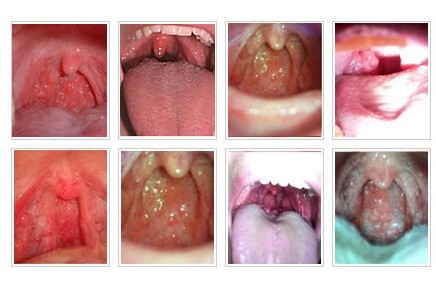

点咨询医生所谓的滤泡性咽炎是由增生性咽炎引起的一种比较常见的咽炎。滤泡性咽炎临床表现为咽部有异物感,灼热,干燥,发痒,轻微疼痛,分泌物粘稠,而且,这种情况是常附于咽后壁,因分泌物刺激而咳嗽,恶心干呕,晨起较轻,午后、入夜较重,所以,及时的采取措施来处理这样的问题对患者的健康才更加有保证。滤泡性咽炎应该怎样治才好?

得了慢性咽炎后,抗原(动物皮屑、尘螨、虫卵蛋白、花粉、动植物蛋白等)随淋巴液流经淋巴滤泡,刺激淋巴滤泡增生,有的演变成浆细胞。浆细胞产生抗体,当抗体输入淋巴液和血液后可作用于抗原,以保护身体的健康。由于抗原的不断刺激,这一过程就不断地周而复始地(或重复地)进行着,淋巴滤泡逐渐增大,进而顶起粘膜,就是我们看到的增生的淋巴滤泡。